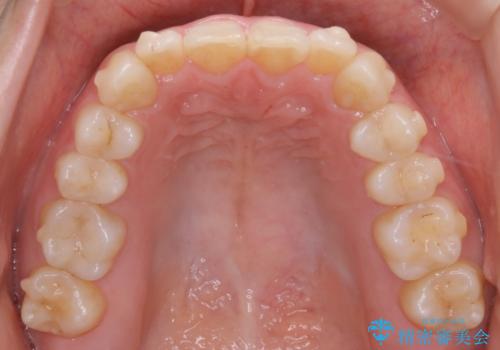

下顎については、歯の側面を削ることをメインにがたつきを改善しました。

今回、奥歯のかみ合わせに問題がなく、前歯のがたつきのみの対応だったため、インビザライン モデレートというものを使用しました。インビザライン モデレートは歯を動かせる枚数が、最大26枚までと制限があります。お口の中の状態をよく精査し、どの種類のインビザラインを使用するかを判断しています。